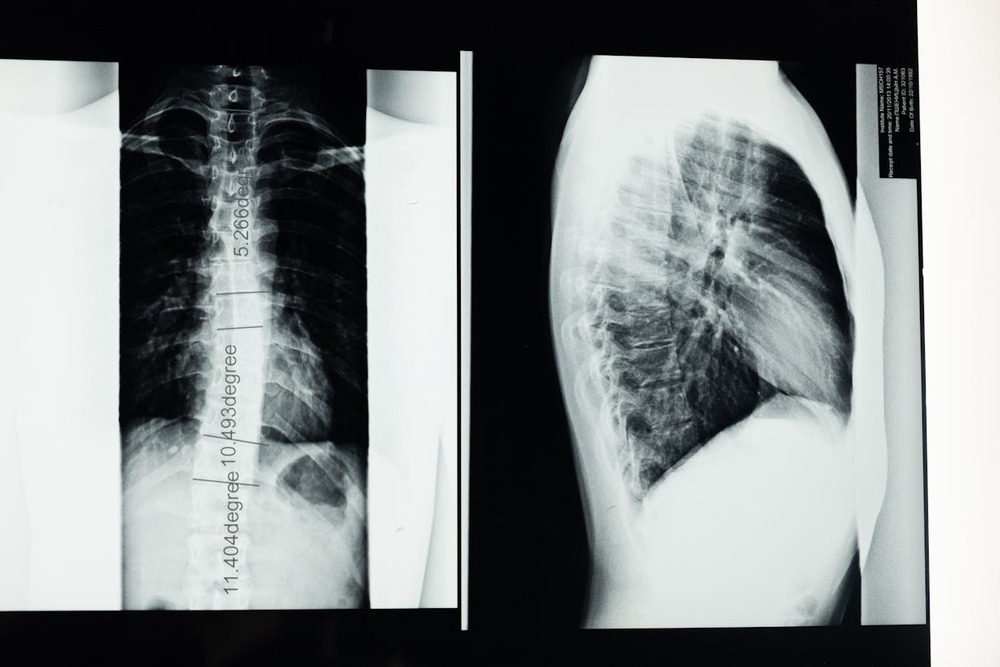

X-rays versus CT, MRI, and myelography

X-rays can help identify fractures, vertebral changes, and some patterns of disc mineralisation. However, they do not directly show the spinal cord, and they are not a reliable way to confirm or rule out IVDD on their own.

CT and MRI provide a much clearer view of the spine and the tissues around it. Myelography (a contrast study around the spinal cord) is sometimes used as well, especially in surgical planning. Your vet will talk you through what each test can and cannot answer in your dog’s case. 5, 6